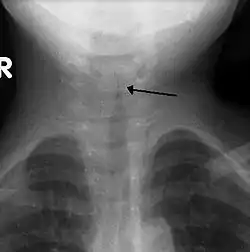

![]() صورة أشعة لعنق طفل مصاب بالخانوق كما هو مشار اليه بالسهم صورة أشعة لعنق طفل مصاب بالخانوق كما هو مشار اليه بالسهم | |

الخانوق يُشخّص سريرياً.[6] تتمثل الخطوة الأولى في استبعاد الظروف المعيقة الأخرى في مجرى الهواء العلوي، خاصة التهاب لسان المزمار، وجود جسم غريب في مجرى الهواء، تضيق تحت المزمار، وذمة وعائية، خراج خلف البلعوم، والتهاب القصبات البكتيرية.[4][6] الأشعة السينية التي تؤخذ أمامياً للرقبة لا يتم تنفيذها بشكل روتيني،[6] لكن إن تم إجراؤها، فإنها قد تُظهر تضيّق ملحوظ في القصبة الهوائية يدعى علامة برج الكنيسة، بسبب تضيق تحت المزمار، والذي يشبه برج الكنيسة. علامة برج الكنيسة أو الصليب تشير إلى التشخيص غير أنها غائبة في نصف الحالات.[5] تم تثبيط تحقيقات أخرى (مثل فحوصات الدم والاستنباتات الفيروسية) وذلك لأنها تسبب تهيجاً لا لزوم له، وبالتالي تفاقم الضغط على مجرى الهواء الخطر.[6] في حين أن الأوساط الفيروسية، والتي يتم الحصول عليها عن طريق الشفط الأنفي البلعومي، يمكن استخدامها للتحقق من السبب الأكيد، لكنها غالباً ما تكون مقيدة في شروط البحث.[3] في حال عدم تحسن الشخص مع العلاج النموذجي والمعياري فإن العدوى البكتيرية ينبغي أن تؤخذ في عين الاعتبار، وهنا لابد من إجراء المزيد من التحقيقات.[4]